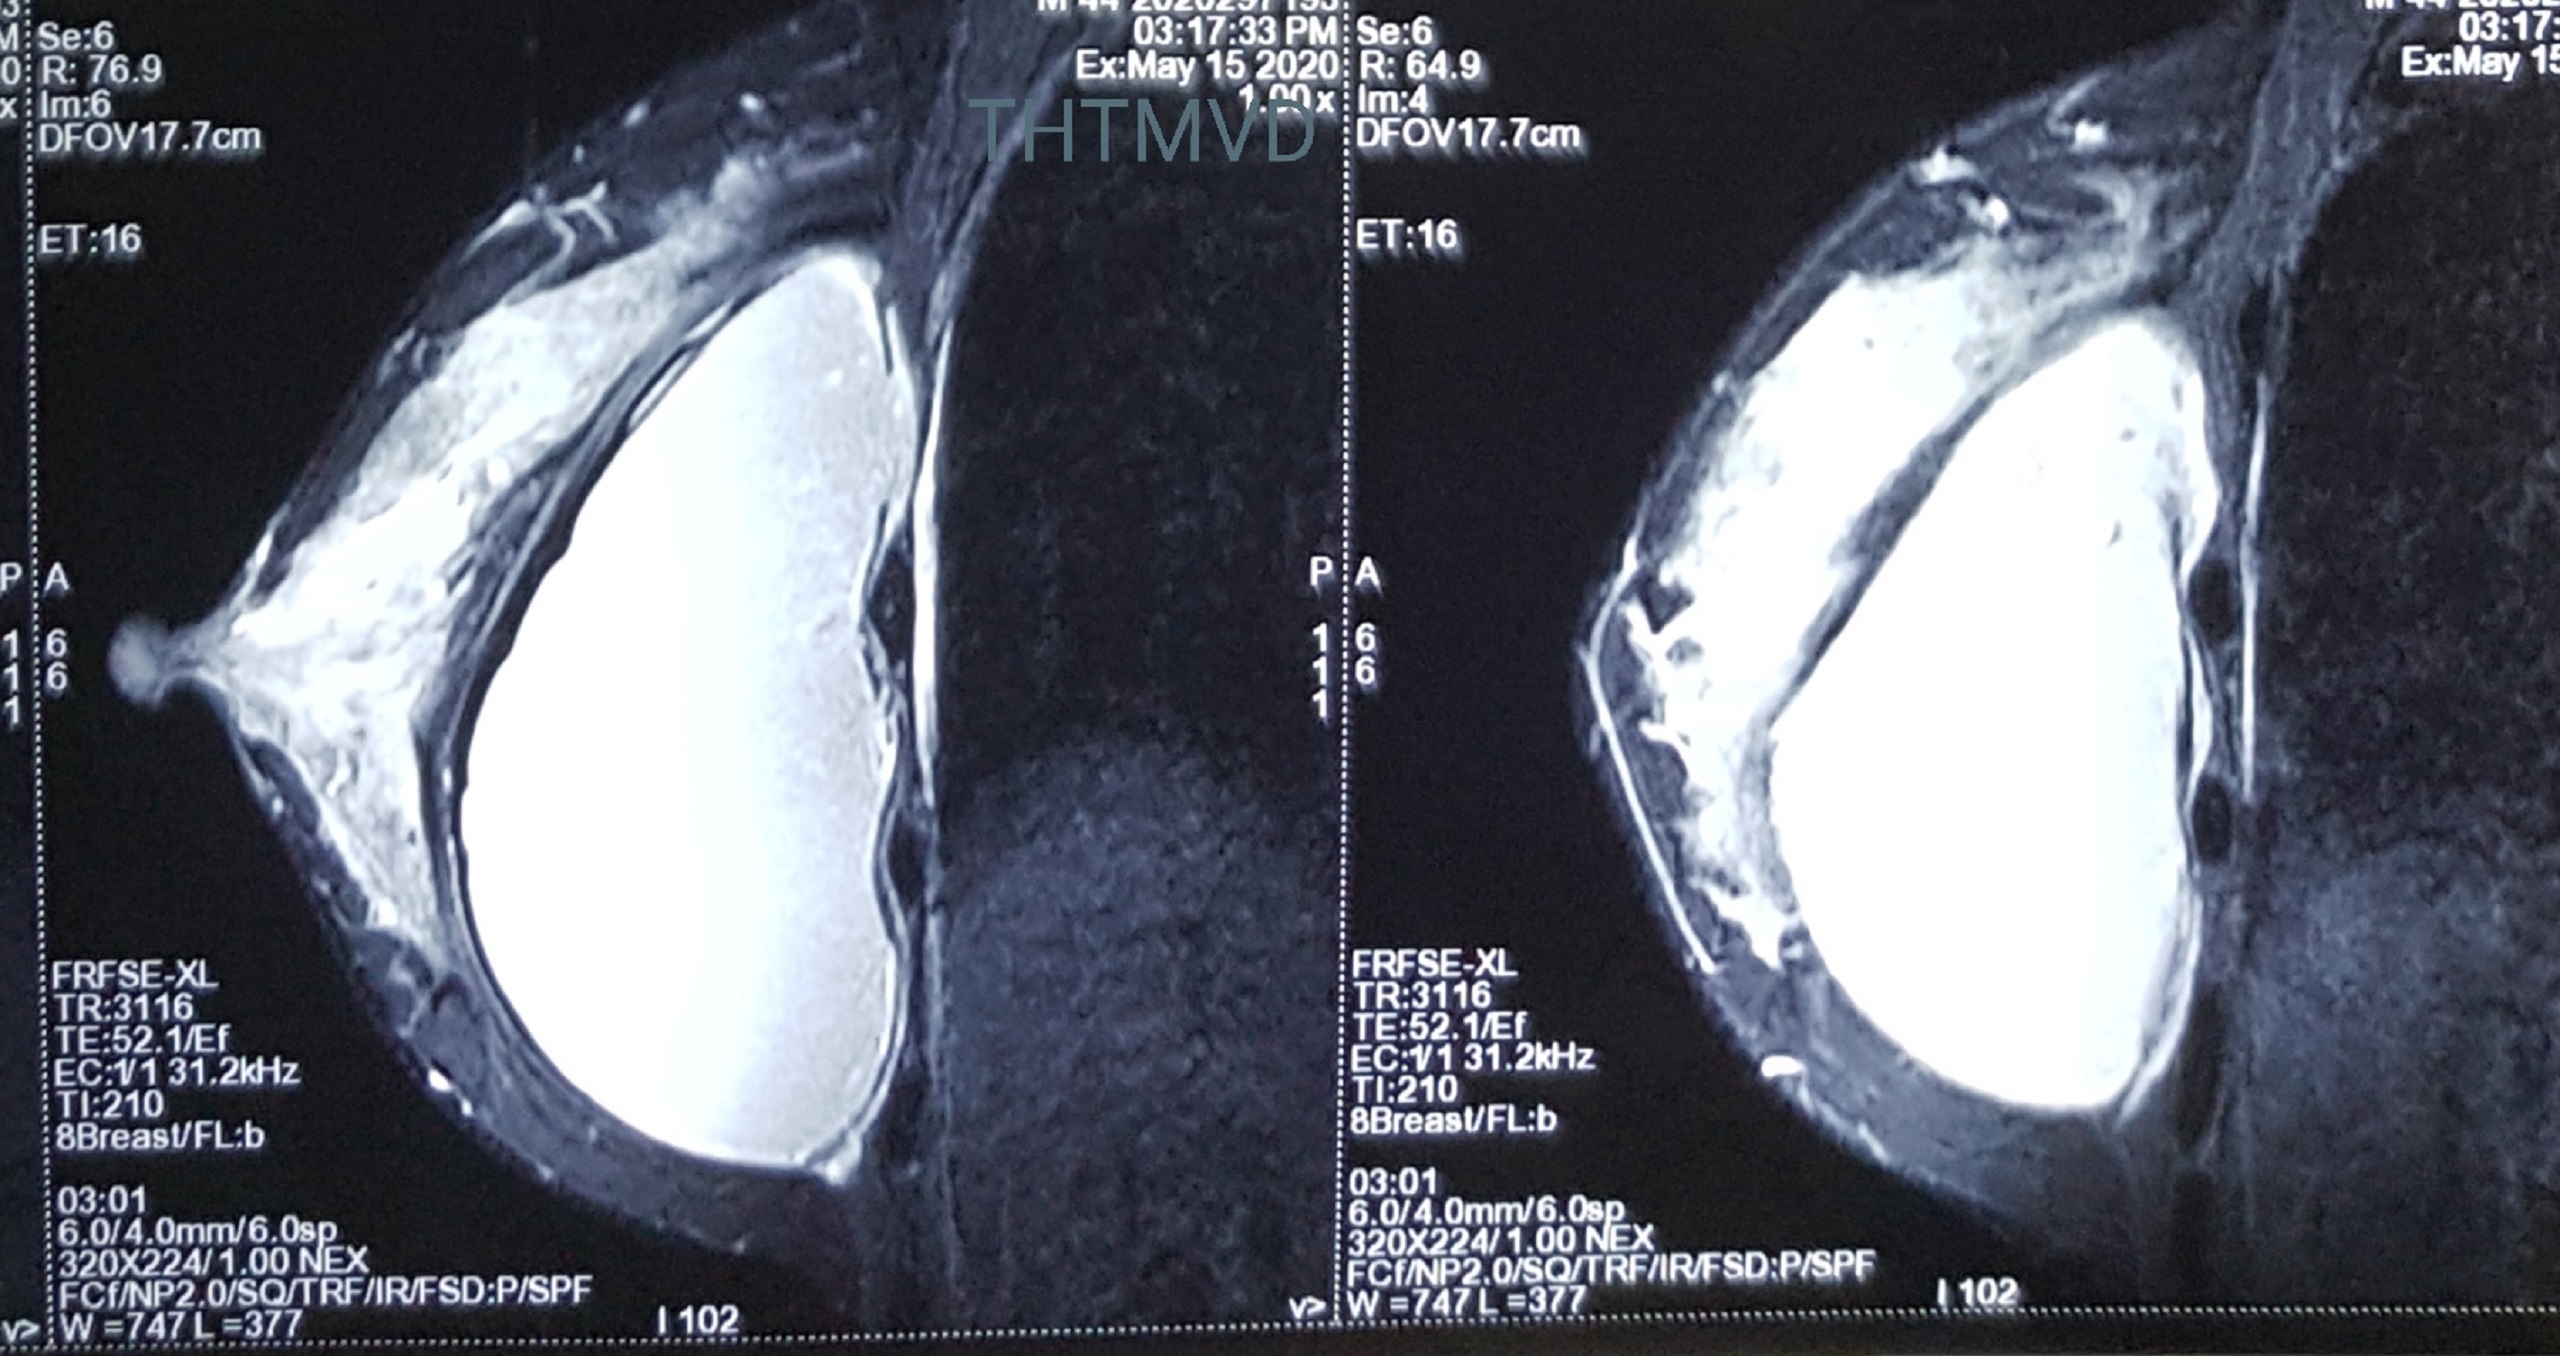

Nhận định có vấn đề bất thường, các bác sĩ đã chỉ định chụp cộng hưởng từ, kết quả cho thấy túi ngực của bệnh nhân đã vỡ từ trước mà không biết. Chị V. ngay lập tức được chỉ định phẫu thuật.

Hình ảnh ngực bệnh nhân qua phim chụp cộng hưởng từ